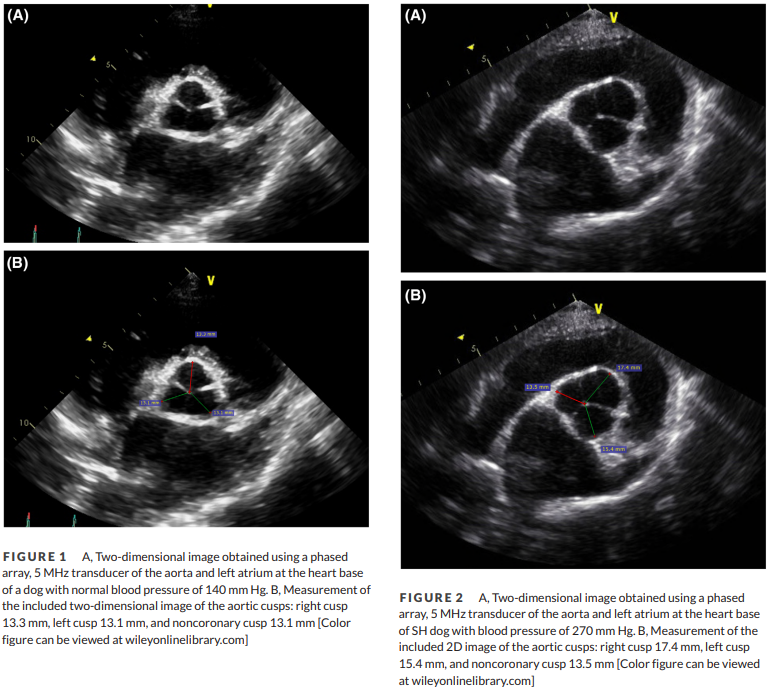

심장초음파 검사시 전신고혈압의 의심 point

판막 대칭성이 감별의 point 라는 말